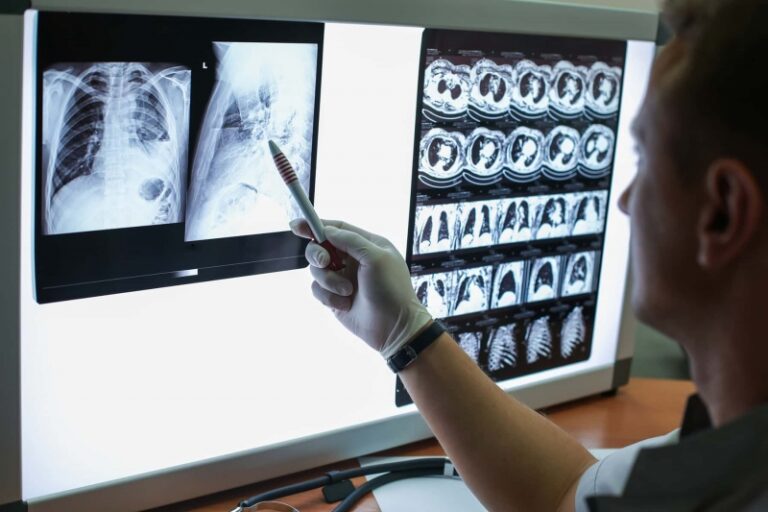

COVID-19 izaziva komplikacije na plućima, bubrezima, kardiovaskularne probleme

Upale pluća, problemi s disanjem, zatajenja bubrega te sepsa ili sistemske upale bile su najčešće komplikacije povezane s COVID-19, što je u skladu s drugim studijama.

Apsolutni rizik da neko s COVID-19 doživi neko od ovih stanja u postocima izgleda ovako: 27,6 posto za upalu pluća, 22,6 posto za zatajenje disajnog sistema, 11,8 posto za zatajenje bubrega i 10,4 posto za sepsu ili sistemsku upalu.

Istraživači su također pronašli povezanost s nizom drugih plućnih i kardiovaskularnih stanja, poput kolabiranih pluća, poremećaja zgrušavanja krvi i upale srca, iako je rizik od njih bio relativno nizak.